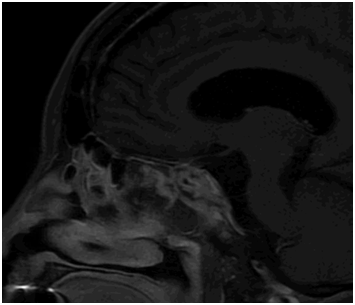

Intraoperatively, a trans-nasal trans-sphenoidal endoscopic approach was utilized. A tan-pink mass with multiple fibrous septations was identified protruding through the floor of the sella. The gross appearance was not inconsistent with the pre-operative diagnosis of macroadenoma. The mass was de-bulked, with residual components at the right optic canal and cavernous sinus determined unresectable and left in situ. A small cerebrospinal fluid leak was noted, which was successfully repaired with a nasoseptal flap. Immediate postoperative MRI (Figure 2) showed satisfactory decompression of the optic chiasm, although a small rind of residual mass and persistent encasement of the right cavernous sinus and right carotid artery narrowing remained.

Figure 2 Sagittal T1 post-contrast MRI 2 days after resection revealing heterogenous packing material in the sella, super-sella, and sphenoid sinus along with interval decompression of mass effect on the optic chiasm with a small rind of residual tumor along the inferior aspect.